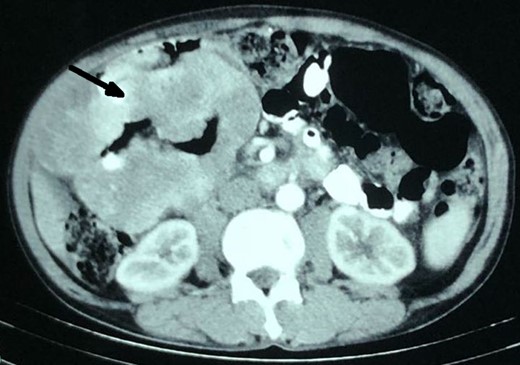

A 55-year-old male, presented with pain upper abdomen, weight loss and anorexia for 4 month. The pain has increased in intensity for past 4 days, with associated malaise and vomiting. On examination, vitals were stable, with an ill-defined tender lump (7 × 8 cm) with localized guarding in the right upper quadrant of abdomen. Blood investigation showed normal hemoglobin (12.8 gm/dl), raised total leukocyte counts (14 600/mm3) and a normal liver and renal function test. Contrast enhanced computed tomography (CT) abdomen revealed an aneurysmal-like dilated, thickened and lobulated hepatic flexure of the colon with homogenous enhancement and no metastases (Fig. 1). Chest X-ray and serum carcinoembryonic antigen (CEA) level were normal. In view of change in the character of pain for the last few days, localized tenderness in the abdomen, leucocytosis and CT findings, diagnosis of right colon malignancy with localized sealed perforation was assumed, and planned for upfront (without colonoscopy and biopsy) surgery.

Contrast CT showing multiple, lobulated enhancing jejunal mesenteric GIST, which mimicked aneurysmal-like dilated (arrow), thickened hepatic flexure of colon.